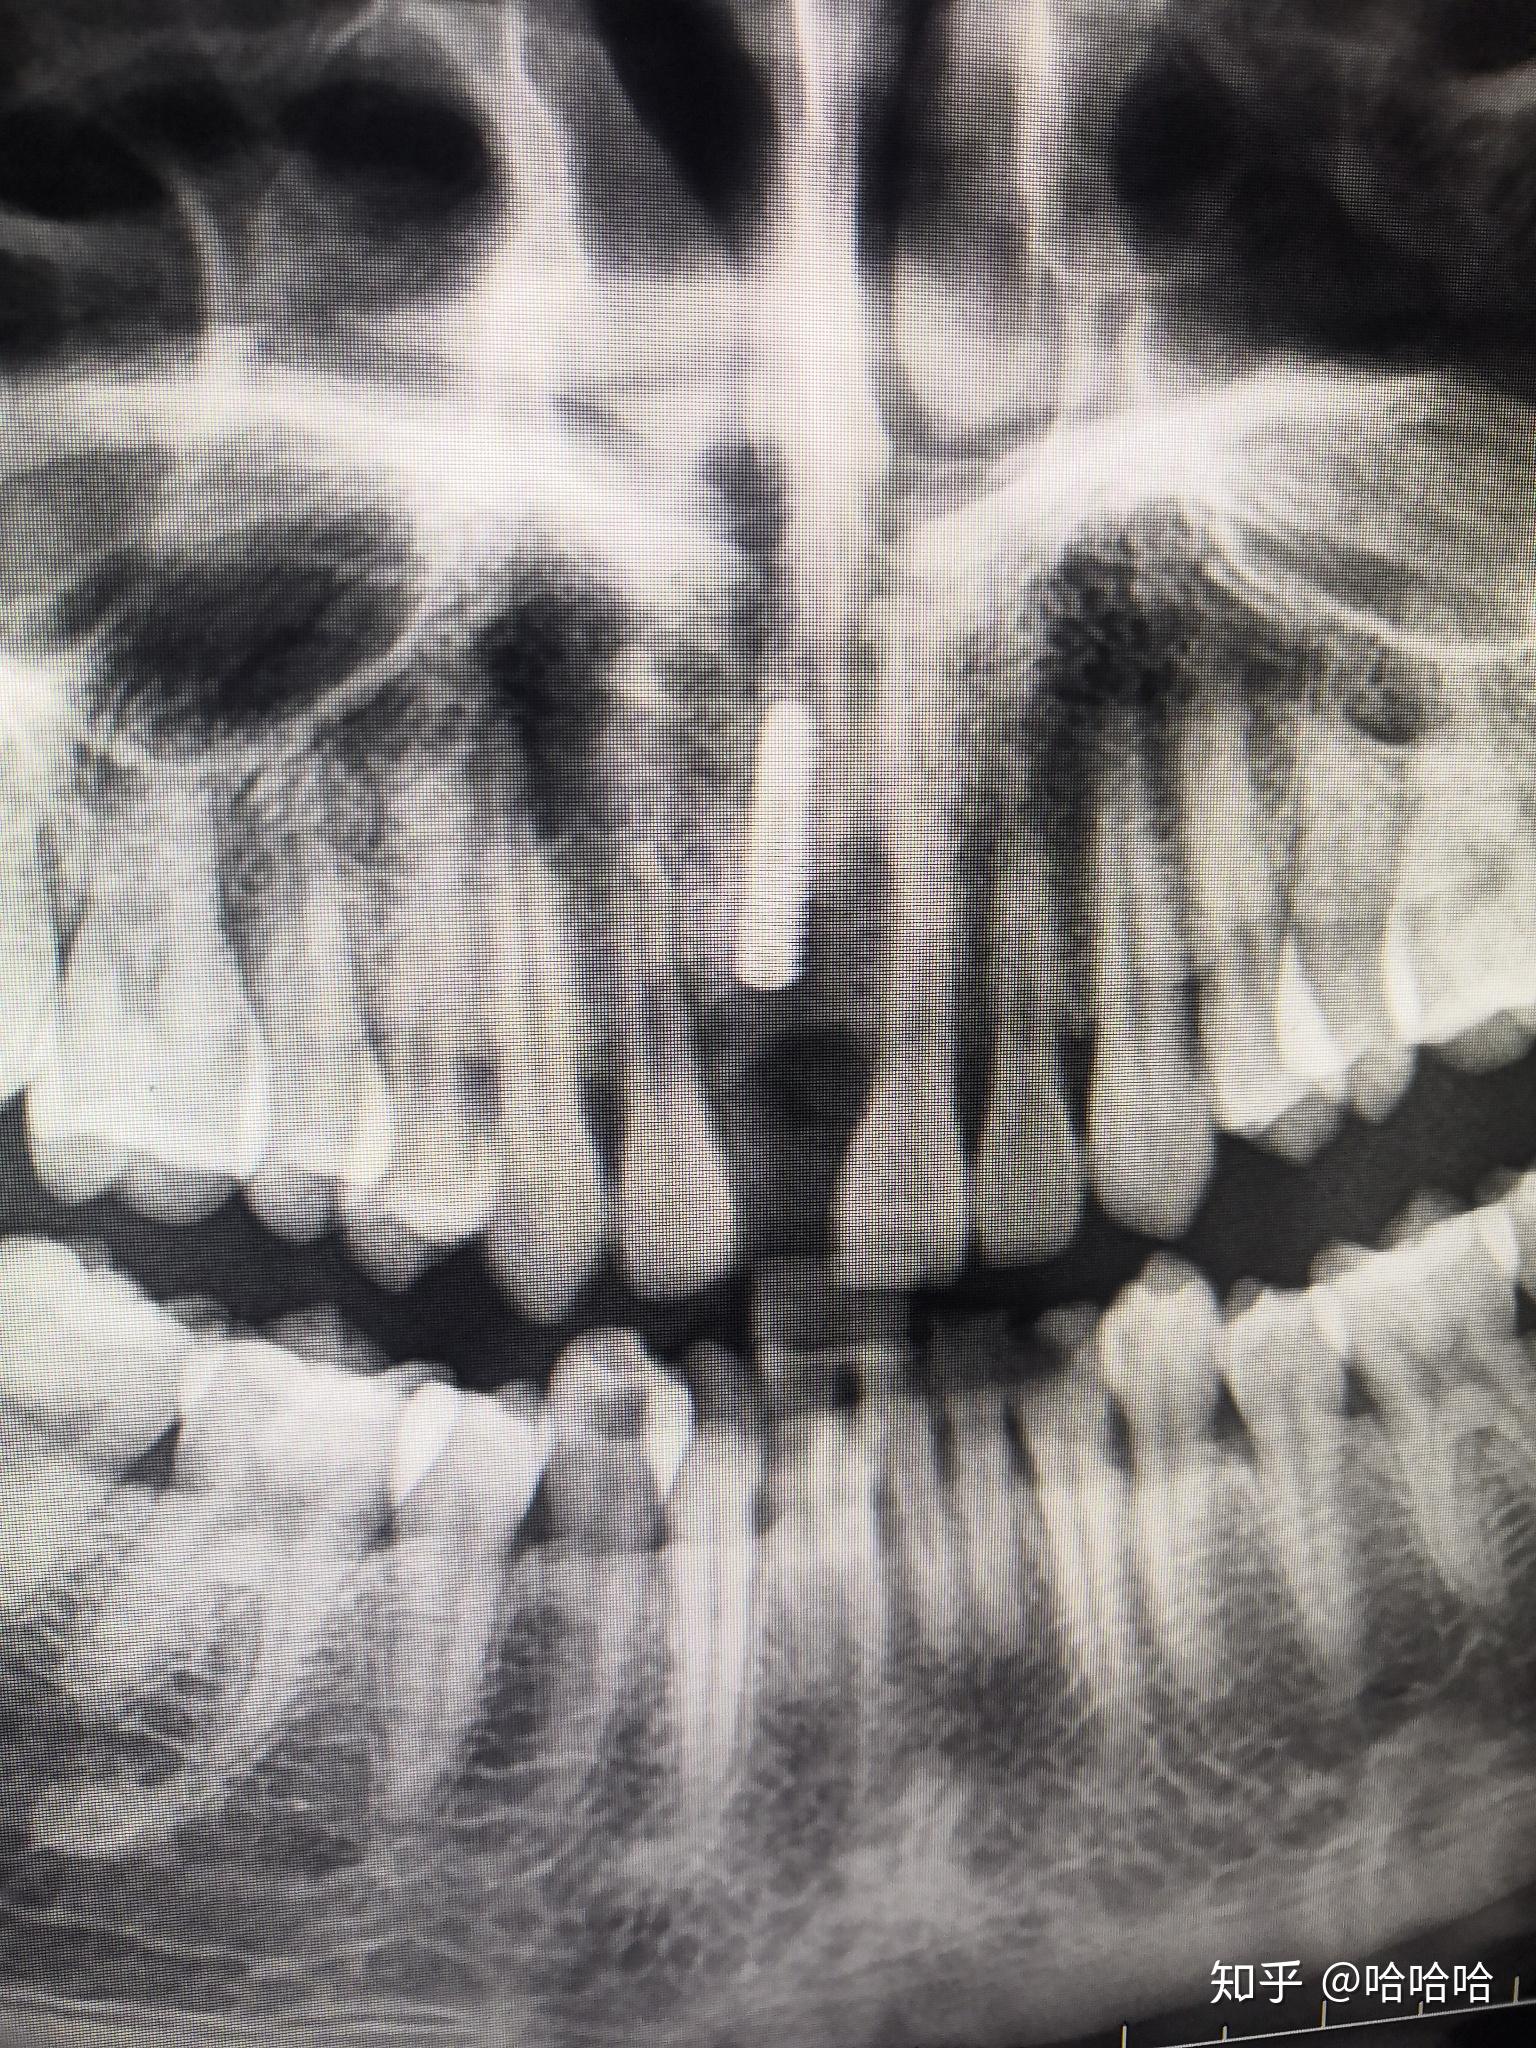

巨型根尖囊肿

图片尺寸620x355